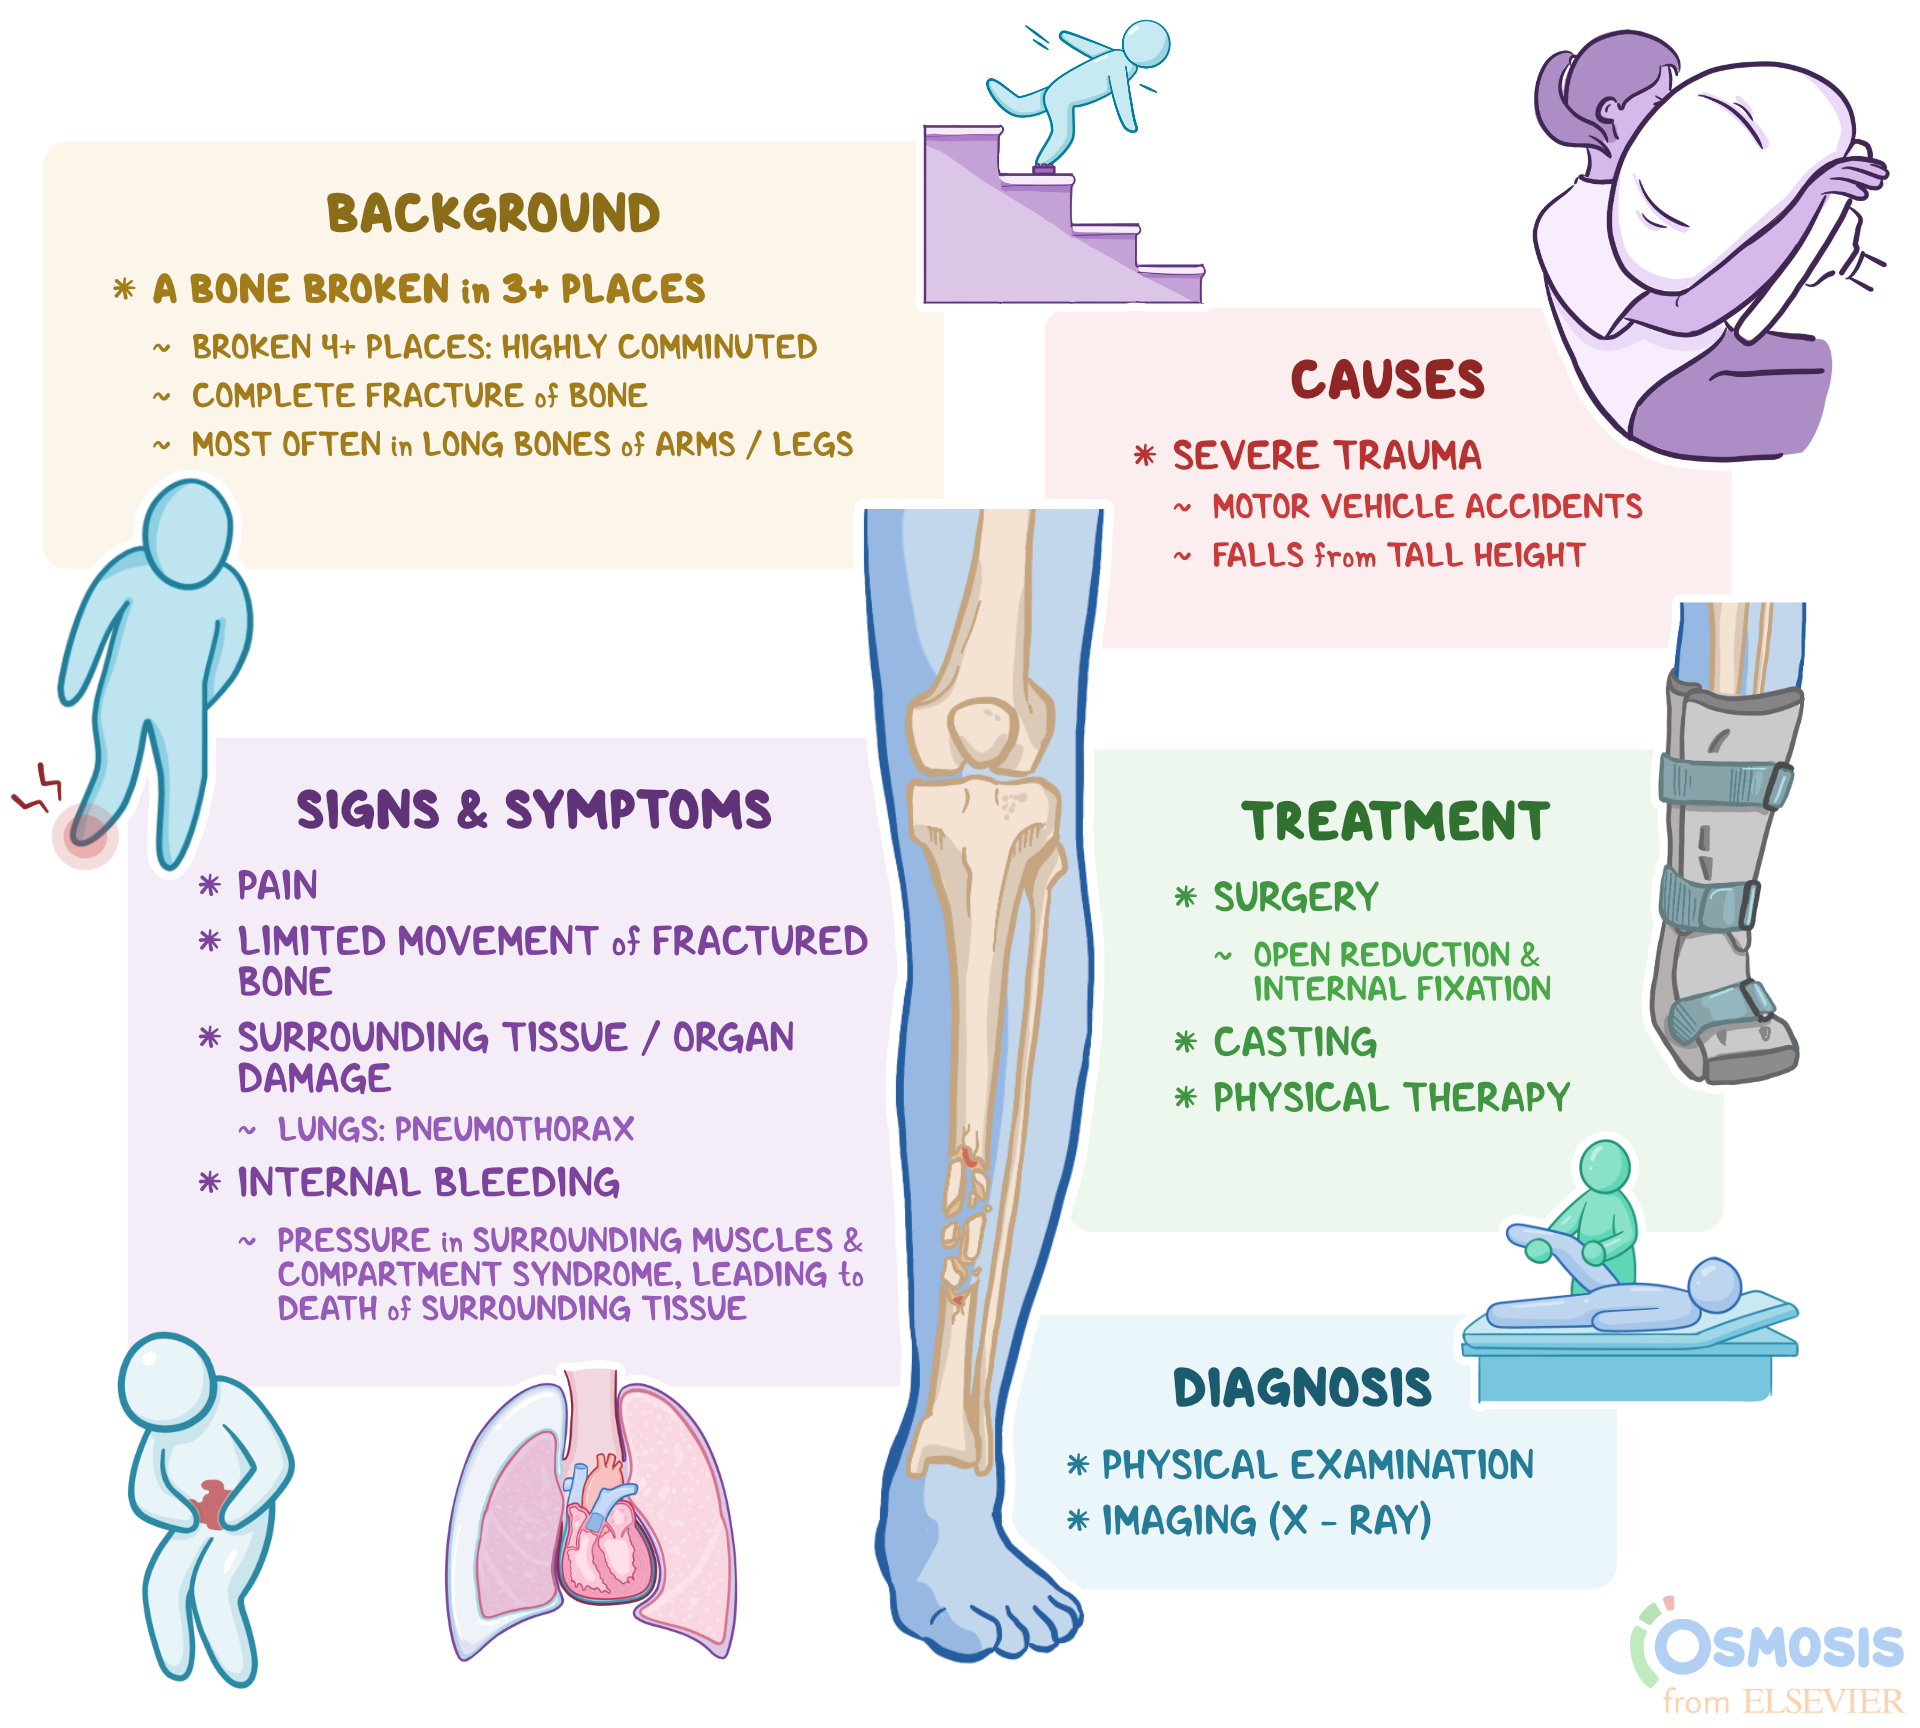

Traumatic Fracture

Trauma and Fractures | OASIS Orthopaedics Melbourne Traumatic Injury & Fracture Treatment - My Toronto Physio Traumatic Spine Fracture - Goodman Campbell All Types of Fractures & Trauma - Dr. Prajaktam Lende's Niva Ortho Care | Orthopedic Surgeon In Nagpur | Orthopedic Doctor in Nagpur | Traumatic Fracture